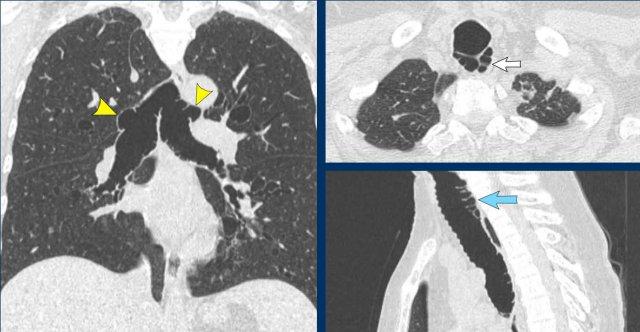

Dưới đây là một số ví dụ về tổn thương dạng nốt hoặc dạng khối trong khí quản và phế quản.

- Ung thư biểu mô tế bào vảy thường có dạng phá hủy với xâm lấn các cấu trúc xung quanh.

- U carcinoid là tổn thương nội phế quản có giới hạn rõ, hiếm khi liên quan đến khí quản.

- Mỡ đại thể có thể gặp trong u hamartoma hoặc u mỡ (lipoma).

- Chất nhầy có tỷ trọng thấp và thường chỉ quan sát được trên cửa sổ phổi.